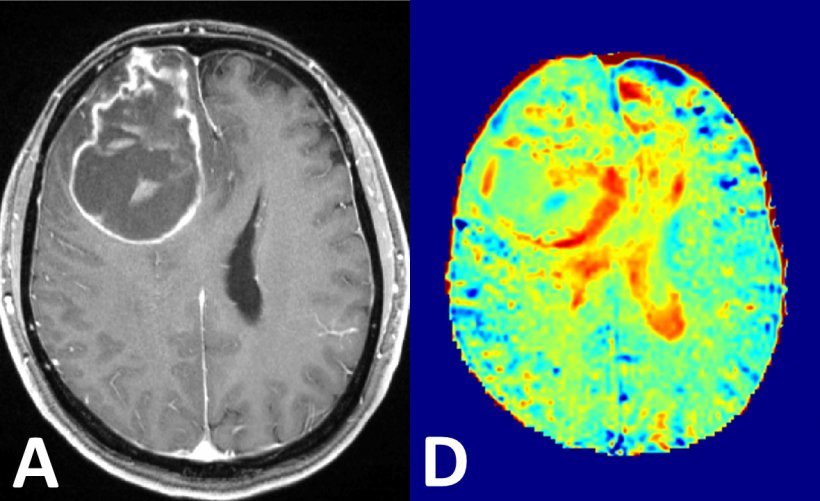

У той час як ПЕТ / КТ відомий як діагностичний наріжний камінь у різних онкологічних рекомендаціях щодо візуалізації завдяки своїй чутливості та морфологічній візуалізації з високою роздільною здатністю, ПЕТ / МРТ має вищу контрастність м’яких тканин і менший вплив радіації. Однак клінічних даних щодо ПЕТ / МРТ недостатньо через відсутність клінічних досліджень з відповідними обсягами вибірки.

У спостережному дослідженні в цілому 1003 обстеження ПЕТ / МРТ всього тіла на 918 пацієнтів з одного центру були порівняні з обстеженнями ПЕТ / КТ всього тіла тих самих пацієнтів. До онкологічних показань належали рак легенів, рак шлунково-кишкового тракту або нейроендокринний рак, гінекологічний рак або рак молочної залози, рак передміхурової залози, лімфома, меланома, рак голови та шиї, рак невідомої первинної та злоякісної хвороби кісток.